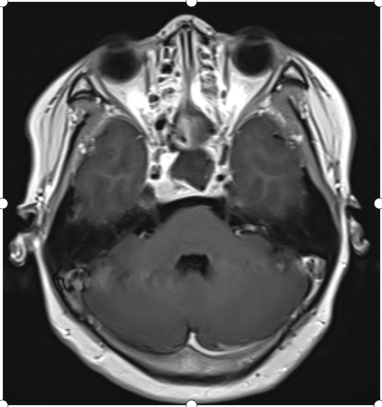

术前核磁共振提示垂体瘤复发